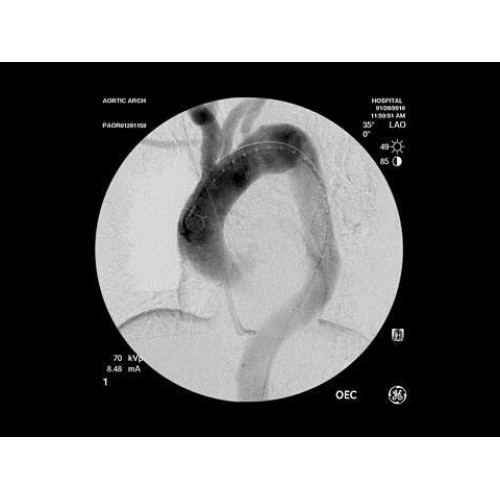

• Кардиохирургические вмешательства и ангиопластика

• Эндоваскулярная нейрохирургия

• Сосудистая хирургия

В ведущих медицинских центрах GE OEC 9900 Elite успешно применяется для проведения сложных кардиологических, нейрохирургических и ортопедических вмешательств. Система доказала свою эффективность при выполнении стентирования коронарных артерий, эмболизации сосудов головного мозга и вертебропластики. Многие учреждения отмечают повышение качества операций после внедрения этого оборудования.